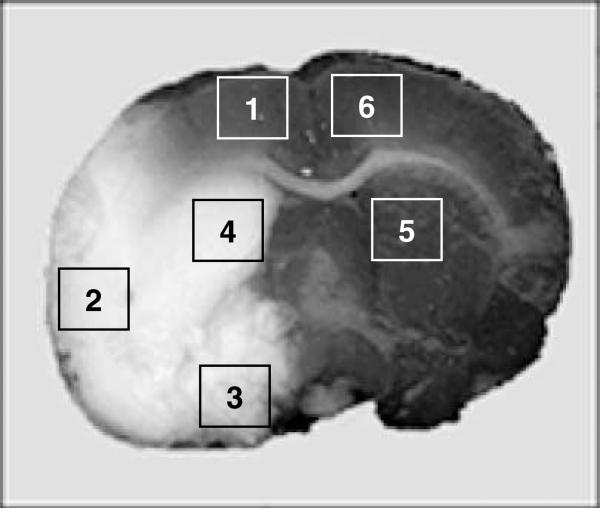

Figure 1.

Regions of the brain evaluated for quantitative ICC; the ischemic hemisphere areas 1 to 4 are in the ischemic or right hemisphere; areas 5 and 6 in the nonischemic or left hemisphere.

Histology

On killing, brains were frozen and stored at –80°C. To determine the infarct size, brains were sectioned (10 μm) at 6 predetermined levels (bregma +2.40, +1.00, –0.40, –1.80, –3.20, and –4.40) and stained with cresyl violet; infarct volume was calculated and corrected for edema (Swanson et al, 1990). Quantitative immunocytochemistry (ICC) was performed on sections at the level of the anterior commissure. Sections were fixed in acetone and methanol and stained with antibodies to CD4 (clone W3/25), CD8 (clone MRC OX-8), B7.1 (CD80; clone 3H5), B7.2 (CD86; clone 24F), MHC I (OX-18), and MHC II (OX-6). OX-18 and OX-6 antibodies were obtained from Pharmingen, San Diego, CA, USA; all other antibodies were obtained from Serotec, Raleigh, NC, USA. Sections were developed using peroxidase and 3,3′-diaminobenzidine (Vector) and counterstained with cresyl violet. The NeuroTACS™ kit (R&D Systems) was used to detect apoptosis. Sections were examined at × 100; the numbers of labeled cells within six different high-power fields in six different brain regions (Figure 1) were counted by two independent investigators masked to treatment status. The phenotype of cells expressing B7.1 was determined using double-label ICC for astrocytes (glial fibrillary acidic protein (GFAP); Sigma), microglia (OX-42; Serotec), and neurons (Neurotrace Nissl stain; Molecular Probes, Carlsbad, CA, USA).